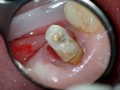

Rozległa torbiel zawiązkowa żuchwy

Paulina Adamska, Maria Mikołajska, Anna Janowska, Anna Starzyńska